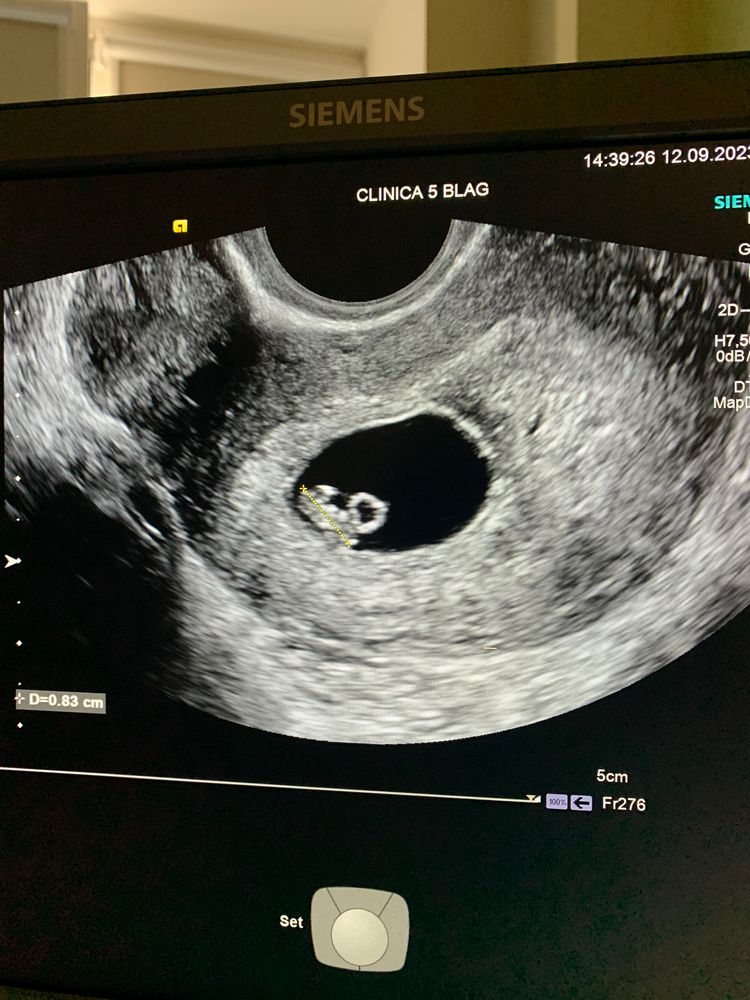

УЗИ 6 недель 6 дней

12.09.2023

Капуста, согласно теории Рамзи, плацента с правой стороны матки указывает на ребёнка мужского пола, а плацента слева - на женское. Метод не научный. Изображение